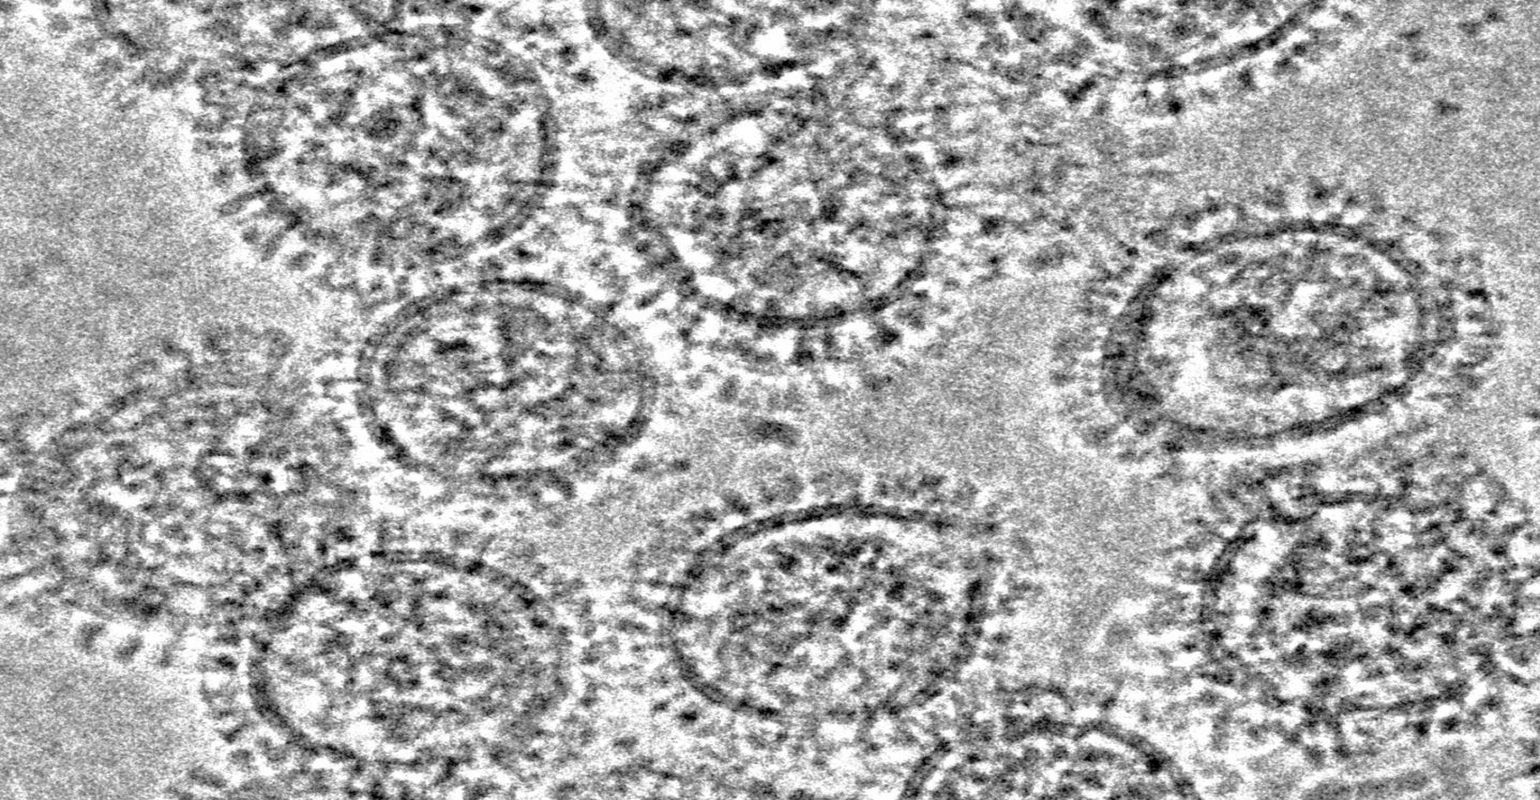

Hemagglutinin and neuraminidase are yin-yang proteins present on the surface of the influenza virus. The former mediates virion attachment and fusion with host cell membranes, while the latter is an enzyme that releases budding progeny virions from the cell surface that remain attached via the hemagglutinin binding.

Hemagglutinin consists of a head domain that contains the receptor binding site that attaches to host cell membranes and a stem domain that connects the head to the virion membrane. Current flu vaccines induce antibodies that recognize the hemagglutinin head and inhibit its ability to mediate viral entry. But the hemagglutinin head undergoes rapid mutation to escape existing antibodies. This generates vaccine-resistant strains of the influenza virus each year, necessitating the yearly mad dash to create a matched vaccine.

The hemagglutinin stem domain, in contrast, is far more resistant to mutations, providing a target for universal flu vaccines, as has been shown by dozens of studies in animal models.

Stem-binding antibodies can block viral entry into host cells by inhibiting hemagglutinin cell fusion activity, but as Yewdell's lab reports, they also inhibit the release of newly replicated virions by blocking neuraminidase molecules in close proximity to hemagglutinin on the virion.